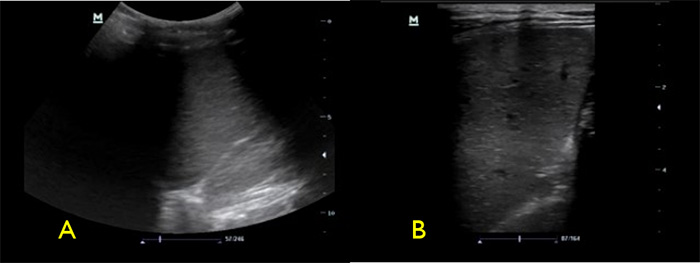

- Periaortic lymph nodes greater than 1cm: OR = 2.6, 21 PPV = 69%, NPV= 27%18

- Periaortic lymph nodes can be hard to identify. As they enlarge, they are easier to see and often lose their central hyperechoic region (hilum). As you scan through a lymph node, they will appear to grow then shrink because of their spherical shape.

Figure 6. Numerous periaortic lymph nodes

Video 8. Proximal aorta with multiple enlarged periaortic lymph nodes

- Ascites (Fig. 6)

- Ascites is a common finding in many disease entities however in the patient with HIV from a TB endemic area, it is highly suggestive of TB.

- With or without fibrinous debris: OR 2.221

- Without fibrinous stranding: PPV= 73% NPV = 33%18

- With fibrinous stranding: PPV = 86% NPV= 41%18

Figure 7. Fibrinous ascites in pelvis sagittal view

Figure 8. RUQ free fluid with fibrinous stranding and hyperechoic liver lesions